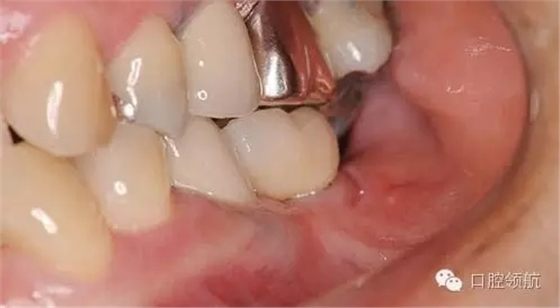

全景X線片上沒發(fā)現(xiàn)有骨吸收現(xiàn)象(圖2),發(fā)現(xiàn)在MGJ附近和種植體周圍齦溝里有白色顆粒的存在(圖3)。

圖3 種植體的邊緣部可以隱約看到幾個(gè)小顆粒,口腔前庭也可以看到散在小顆粒。